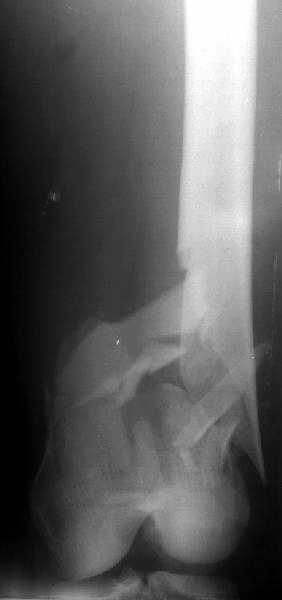

The antegrade nail in the case shown is probably into the knee joint slightly.

This case looks great but there must be some risk of splitting the condyles or other knee joint injury when driving an antegrade nail this distal. The antegrade nail also has entry site problems including variable injury to the hip muscles, heterotopic ossification, femoral neck fracture, and positioning difficulties. Overall the entry site problems seem about the same for the two techniques. If that is the case then the decision might come down to which one offers better distal fixation and that might be retrograde nail. If there are more entry site problems with retrograde nail than antegrade the antegrade nailing might be preferable even if the distal fixation isn't quite as good or reliable.

So, to me, it is a trade-off between benefits and risks for specific fracture patterns. In this case of a very distal femur shaft fracture the antegrade nail driven very distal in the femur looks extremely good. Without a comparative series we are left to base decisions on general principles, theory and related experience.